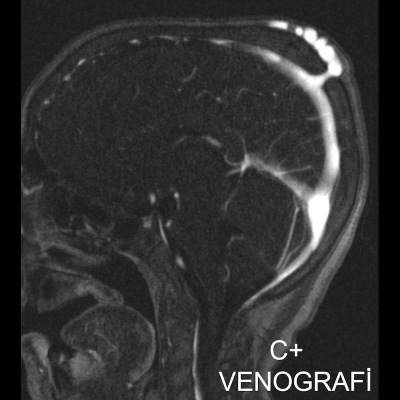

1. A) Kontrastlı FLAIR aksiyel görüntüde ve sagital T2A görüntüde vertekste orta hatta cilt altında dilate tortiyoze vasküler kollateraller (oklar). Paryetal kemikte orta hatta defekt (ok) ve defekt ile ilişkili vasküler yapıların cilt altı yumuşak dokulara uzanımı izlenmektedir.

2. B) Kontrastlı MR venografide orta hatta cilt altı dilate (oklar), tortiyoze emisserian vaskuler yapıların superior sagital sinus ile ilişkisi ve devamlılığı (ok) izlenmektedir.

6. En tanımlayıcı görüntüleme yöntemi MR venografidir.

7. İntrakraniyal ve ekstrakraniyal venöz yapıların ilişkisi net şekilde gösterilir.

8. Lezyonun süperior sagittal sinüs veya diğer venöz sinüslerle bağlantısı doğrulanır.